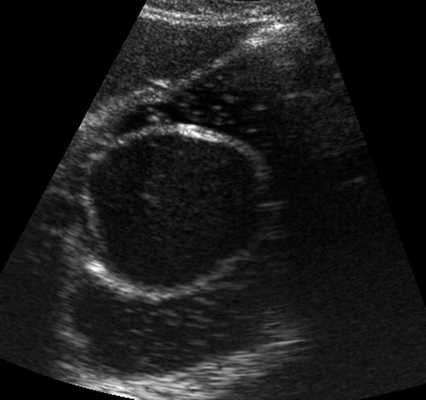

При УЗИ органов брюшной полости в эпигастральной области слева, в проекции желудка (в его просвете) определяется округлое образование, размером 53,1x49,6x45,6 мм, с четкими ровными контурами, по структуре анэхогенное, однородное, с наличием эхоплотной стенки толщиной до 4,1 мм. При наполнении желудка жидкостью создается впечатление, что образование исходит из его задней стенки, так как оно фиксировано к ней и не смещается при перемене пациенткой положения тела и кашлевом толчке (рис. 1). В режиме цветового допплеровского картирования данных о наличии кровотока в капсуле образования не получено. Заключение: киста (кистозное образование), исходящее из стенки или расположенное в полости желудка.

Рис. 1. УЗ-картина дупликационной кисты в просвете желудка, В-режим.